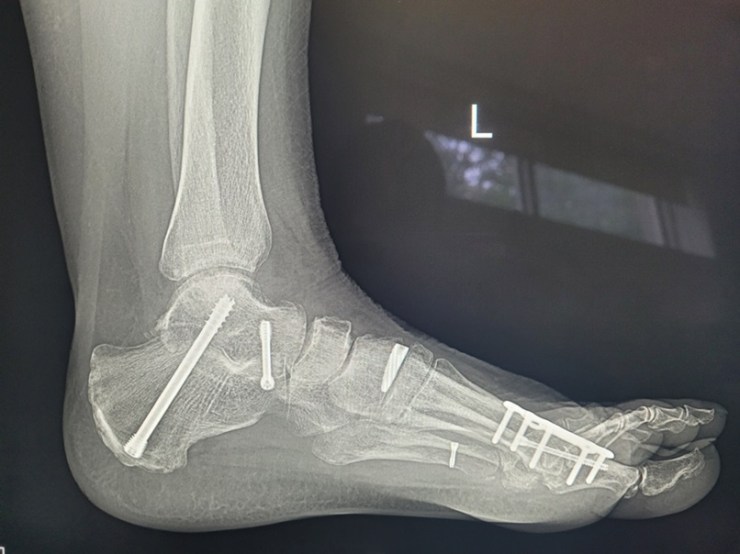

This issue will not apply to all surgeries either. It depends how long your post-op period is AND the degree of immobility required. For example, I’ve had both ankles fused. Same post-op period in both cases. However, with the left ankle I could drive four weeks earlier than with the right ankle and that four weeks, plus an additional, unrelated, hospitalisation, were enough to make what was, in my case, a major difference.

When I had the left ankle done in 2023, by the time I was in a moonboot and on crutches I could drive to the gym and do the weighted back exercises I needed to do to maintain my posterior chain strength. With the right ankle, obviously I couldn’t drive for an additional month. Then, two weeks after I could drive, I was back in hospital for a nasal/sinus infection. Essentially immobile again.